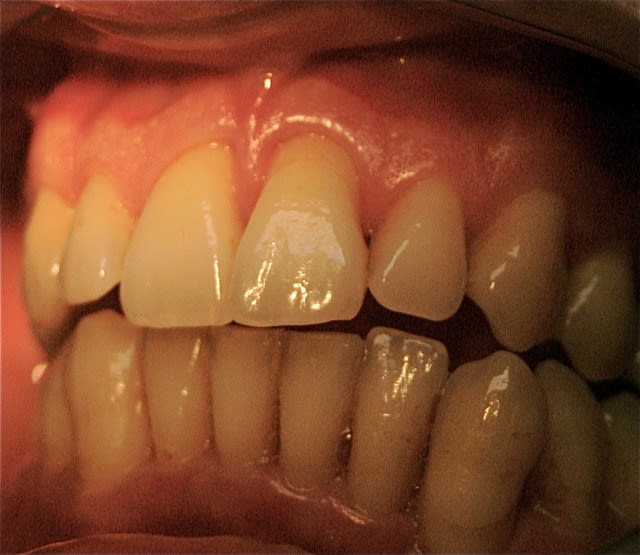

je peux vous soumettre quelques clichés, je crois intéressants ...j'ai investit dans du matériel photo pour vous séduire, acheté des habits sérieux...

toujours aucune extractions depuis 8 ans, sur des cas de paro nommé irréparable par les plus grands parodontistes de France et de suisse! LOL

lus de 250 cas extrêmes et difficiles traités prouvent que nous sommes bien en présence d'une blessure souillée et qu'il suffit de la traiter comme toute blessure souillée.

Les photos que tu montres ne donnent aucun renseignement quand à la guérison du parodonte (Ah oui , pardon ce n'est pas une maladie ).

tes contentions sont dégueulasses même sur des photos de mauvaise qualité peu importe qu'elles soient linguales ou vestibulaires c'est un rail de composite point barre !